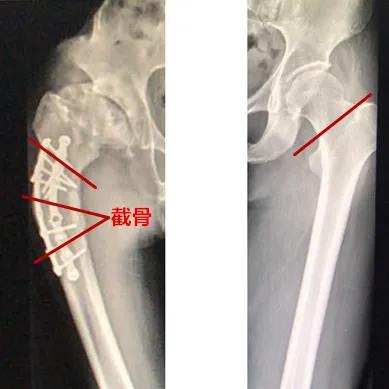

树兰(杭州)医院骨科林道超副主任医师首先画图讲解了一下,左边是一般情况下的全髋置换手术,把坏死的股骨头与髋臼一同切除置换;而右边这是老张即将面临的手术,比常规手术还增加了“截骨”一环。

钢板断裂后,股骨畸形生长弯曲,右腿缩短达7cm,这也是患者一直坡行的原因,如何截骨,重新把股骨“拉直”呢?

医生想出了“三角形”截骨,上图为老张侧面拍片的视角,医生术前为他设计的手术方案,包括切除的位置和角度。

术中截骨